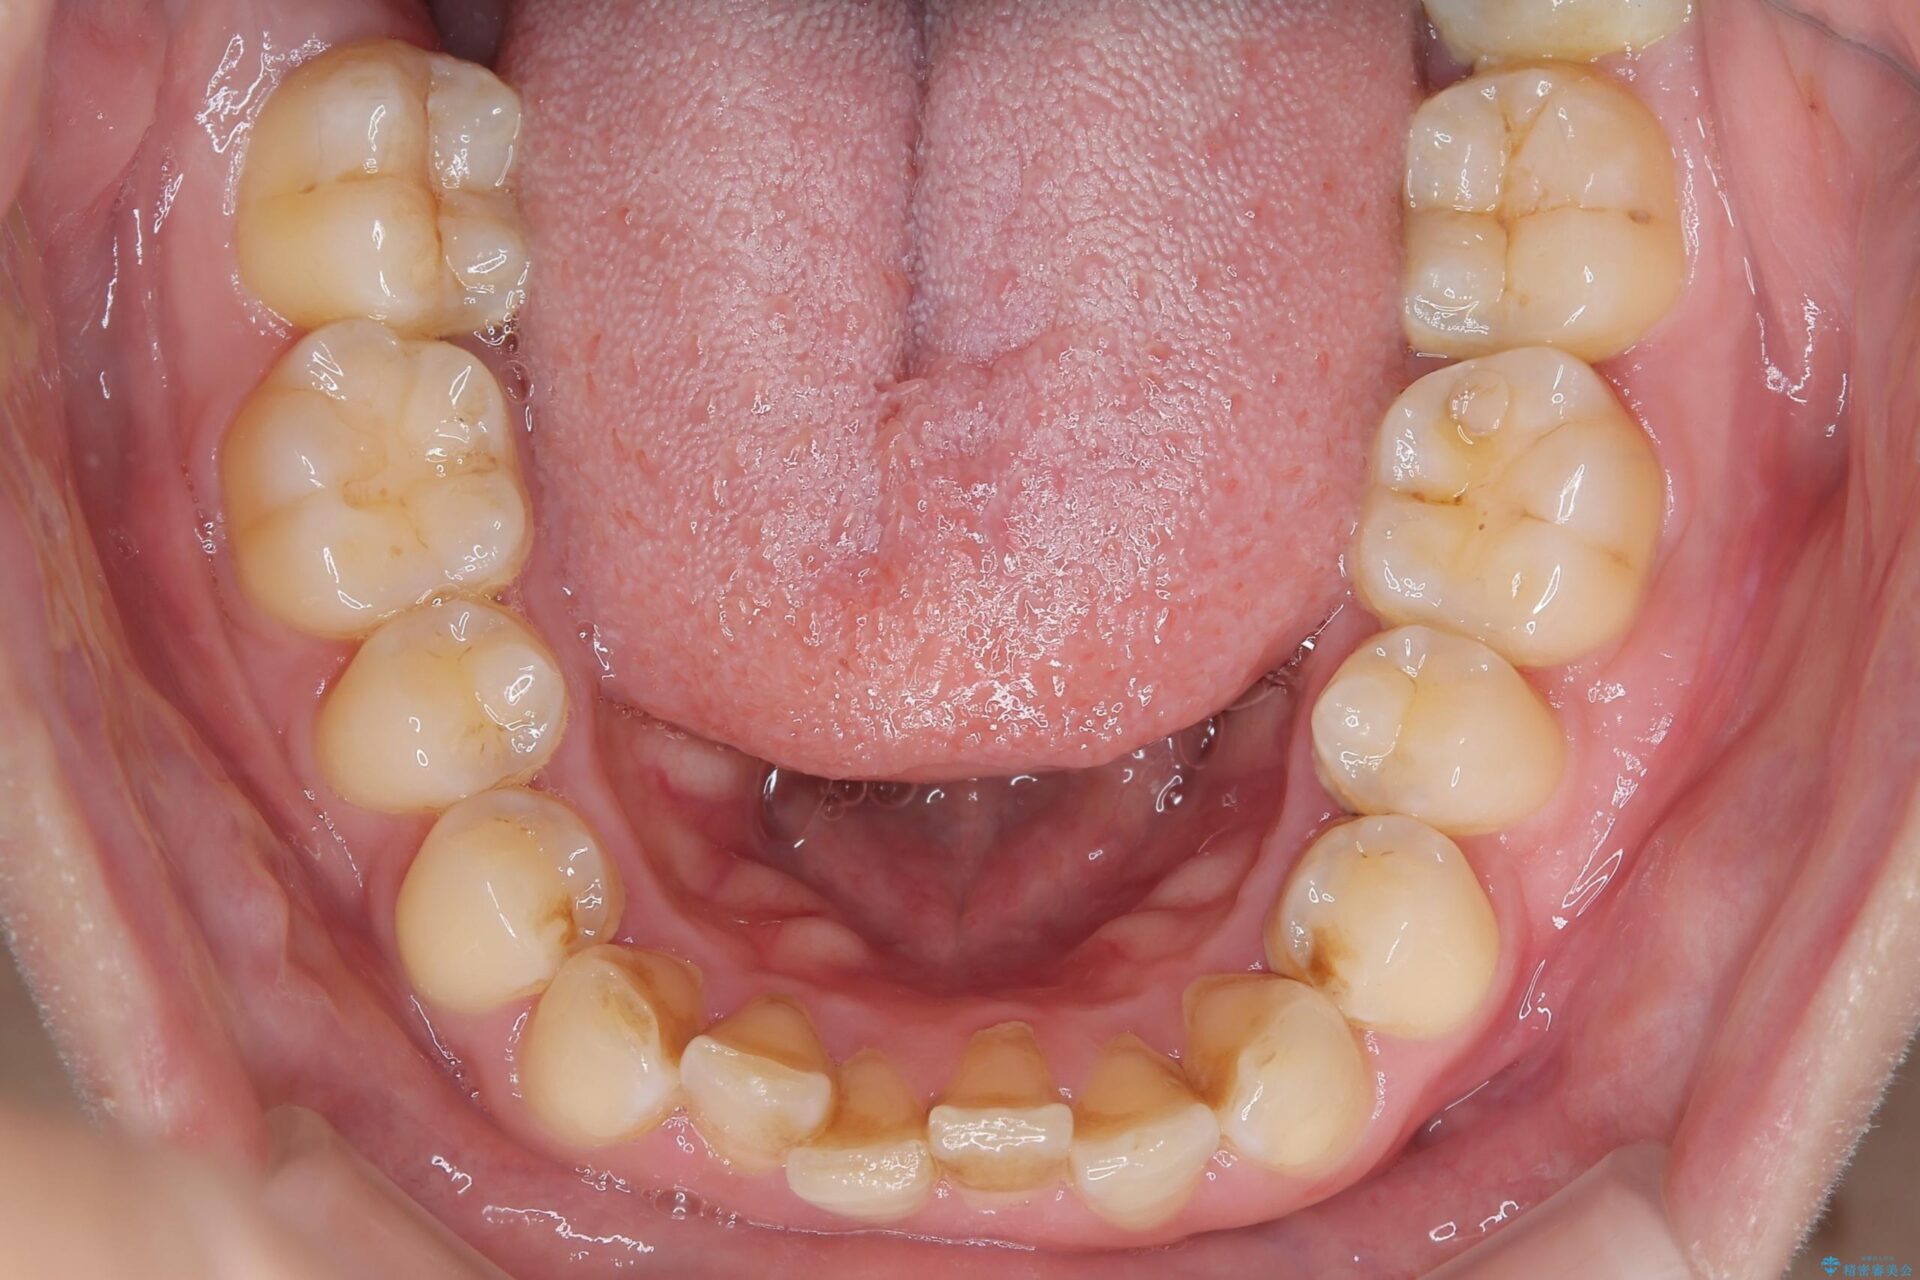

下の前歯のがたつき改善にはIPR(歯と歯の間を削る処置)を行いました。

ゴム掛けを頑張っていただいたので、噛みあわせも改善され綺麗な歯並びになりました。